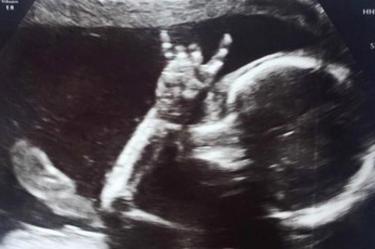

¡Que viva el rock! Bebé sorprende a padres en ecografía

Dos padres amantes de la música transmitieron sus gustos musicales a su hija, quien en un ultrasonido mostró una señal de rock

En esta ocasión, dos papás británicos sabían que su hija compartiría el amor por la música al igual que ellos. E so lo dejó ver una ecografía que se hizo Jodie Lee, la mamá de 31 años.

Jodie, junto a su pareja Davie Langham, de 32, acudieron a un médico en la zona este de Sussex, Inglaterra. Cuando vieron a su bebé, de 24 semanas, hacer la señal rockera quedaron sorprendidos y emocionados.

A pesar de que la fotografía no es reciente, pues Isla ya tiene 18 meses, apenas la compartieron y por eso se viralizó.

Algo nos queda claro: Isla ya rockeaba desde antes de nacer.